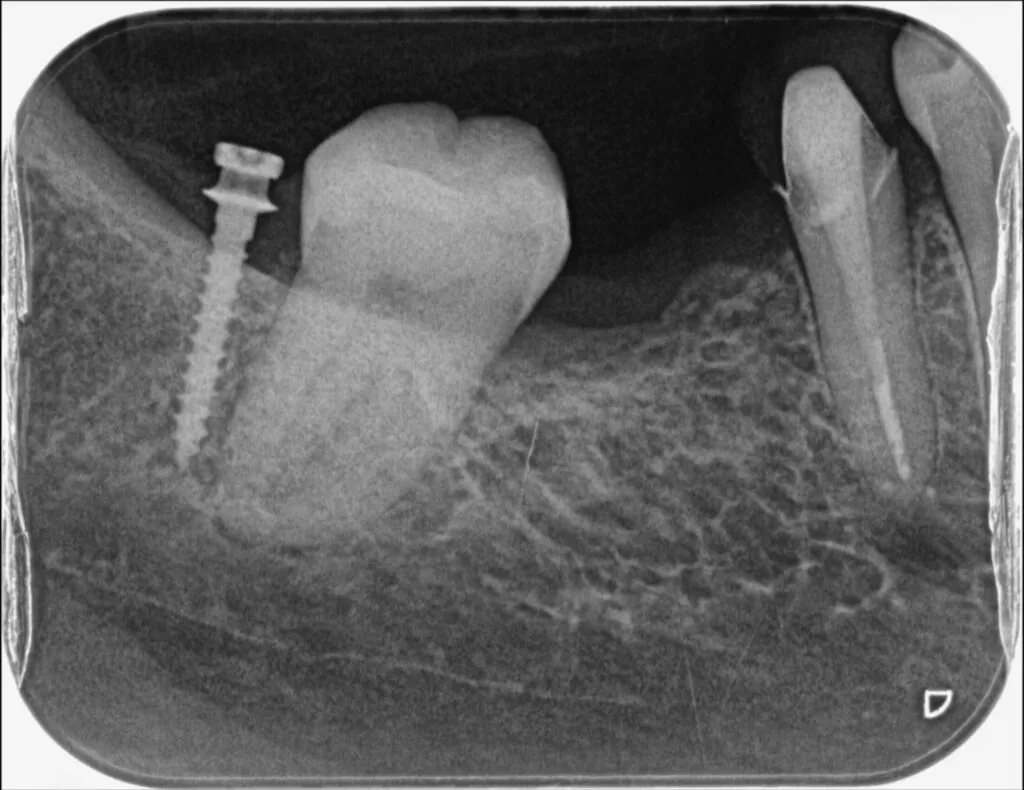

隙間があいている前歯を移動させる場合や、傾いている歯をまっすぐに修正する場合に有効な治療法です。またむし歯が骨の中まで進行した場合、通常は歯を抜くことになりますが、歯を引っ張りあげることで、保存できる場合もあります。